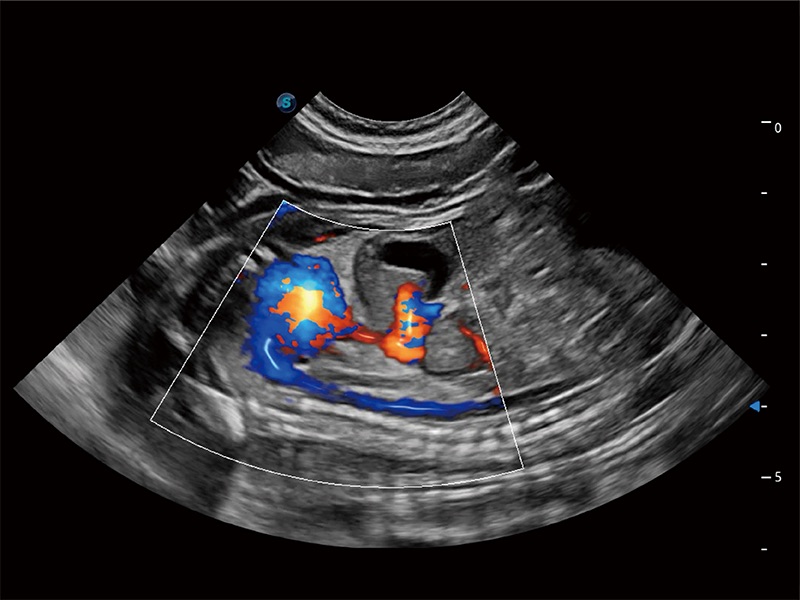

ProPet 80 配备了丰富的心脏探头群、先进的成像技术和专业的心脏测量工具,可帮助动物医生为不同体型和生理结构的动物提供心脏和心肌功能的全面评估。

非线性融合造影成像充分利用谐波和基波信号,为难以观察的血流进行增强显像。可用于线阵、凸阵、微凸阵、相控阵探头。